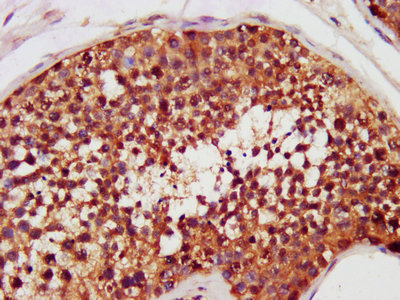

IHC image of CSB-RA828105A0HU diluted at 1:100 and staining in paraffin-embedded human placenta tissue performed on a Leica BondTM system. After dewaxing and hydration, antigen retrieval was mediated by high pressure in a citrate buffer (pH 6.0). Section was blocked with 10% normal goat serum 30min at RT. Then primary antibody (1% BSA) was incubated at 4°C overnight. The primary is detected by a Goat anti-rabbit polymer IgG labeled by HRP and visualized using 0.05% DAB.